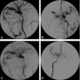

A carotid-cavernous fistula results from an abnormal communication between the arterial and venous systems within the cavernous sinus in the skull. It is a type of arteriovenous fistula. [Source: Wikipedia ]